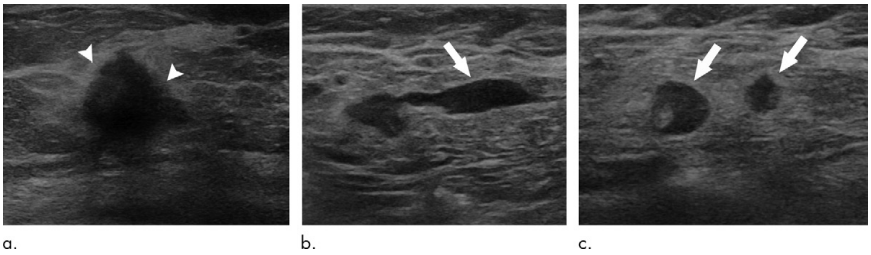

图1.一例T2N2M0期HR+/HER2-乳腺癌患者的腋窝超声表现[3]